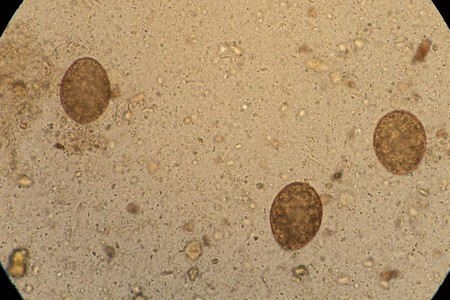

Яйца аскарид выглядят как продолговатые (реже — круглые) фрагменты темно-желтого цвета. Оболочка яиц этих глистов имеет характерную бугристость. Они могут быть оплодотворенными или неоплодотворенными, в первых хорошо просматривается зародыш. Аскариды долгое время живут вне человека и не погибают даже при очень низких температурах.

Фото яиц аскарид